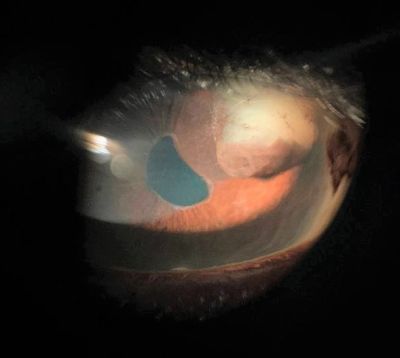

Cysts may have a round or collapsed appearance. Iris pigment epithelial cysts can be located on the anterior or posterior surface of the iris. They have a brown/black, velvety appearance and typically do not transilluminate. Iris stromal cysts appear as clear masses on the anterior surface of the iris and do transilluminate.[12]

Iris cysts secondary to trauma and subsequent epithelial implantation appear as serous or solid in continuity with the wound with or without membranes on the anterior iris surface.

It is important to rule out iris melanoma when evaluating an iris cyst. Iris melanomas appear as a brown lesion arising from the stroma. Unlike primary iris pigment epithelium cysts, they can be variably colored, maintain stable contour even after dilation. Presence of sentinel vessels and intrinsic vessels within the lesion are suggestive of a solid tumor rather than a benign cyst. UBM is very important to analyze the content of the iris cyst and to exclude malignancy.

Ultrasound biomicroscopy (UBM) is the gold standard for imaging large iris cysts. Iris cysts appear round or ovoid with a thin, hyperechoic wall (due to the epithelial cell lining) and a hypoechoic interior (due to its fluid contents). [13]

- Images courtesy of The Robert Cizik Eye Clinic, Houston, TX.